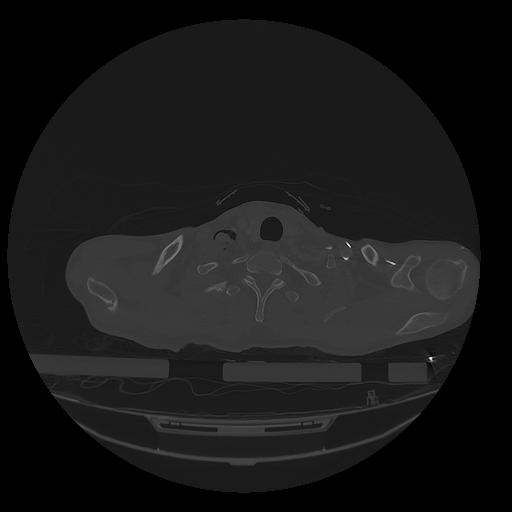

31 PULMON,CE,Vol,1.0,PULMON,,